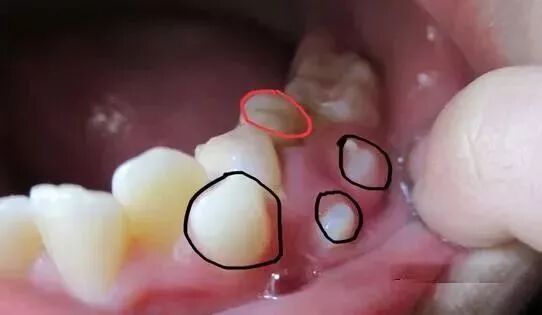

⑵一部分孩子的两个门牙会出现异常的多生牙或者上唇系带附着过低等造成的门牙之间间隙过大的情况,是不会自行消失。多生牙指在牙齿发育时,牙齿的数量比正常情况多。多生牙大多位于两上门牙之间,会影响两个门牙间缝隙的正常闭合,应当及时检查及治疗。

因此,若是家长发现小朋友在换牙期间两上门牙间出现缝隙,千万不要将正常的生理现象和病理状态相混淆,尤其不能自行将橡皮圈等套在有缝隙的牙齿上造成牙齿和牙龈的损伤。